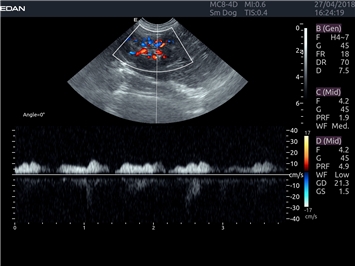

EDAN Acclarix LX4 VET

EDAN Acclarix LX4 VET представляет собой профессиональную ультразвуковую систему, специально разработанную для ветеринарных исследований. Сочетание стабильности, высокой производительности и эффективности делает эту систему идеальным выбором для современной ветеринарной практики.

Цветовой допплер:

Да

Импульсно-волновой допплер:

Триплексное сканирование:

Трехмерная реконструкция ЦДК: